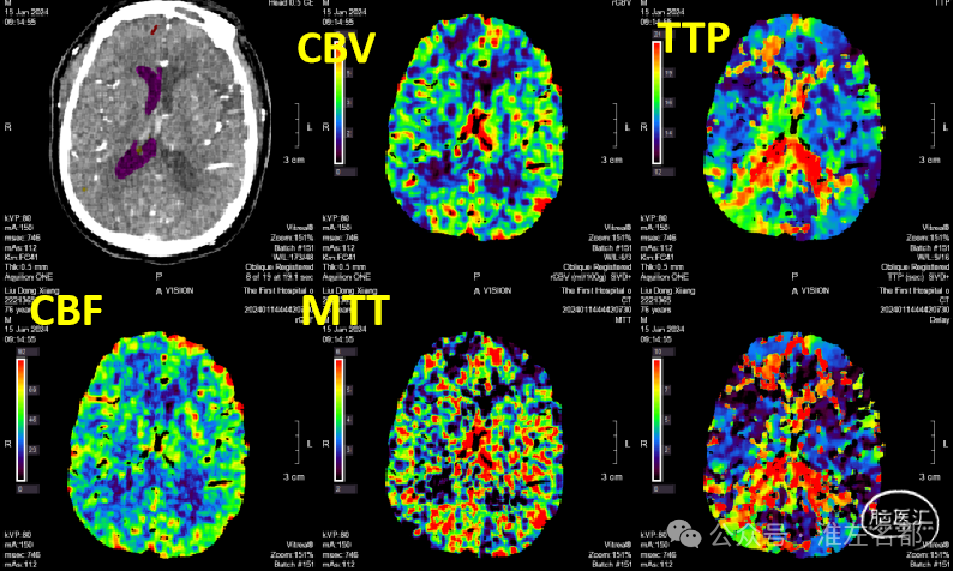

急诊多模式CT

CT平扫:未及明确异常。

颅脑CTA:右侧大脑前动脉A2段局部管腔严重狭窄,右侧大脑前动脉A1段未发育,左侧大脑前动脉A1段粗大。

脑CTP:右侧大脑前动脉供血区局部TTP延长,相应区域CBF和CBV未见明显异常。

本病例有力地展示了脑卒中急诊多模式CT评估技术对症状性脑动脉狭窄患者的诊治价值。

首先,患者发病到急诊时间在24小时内,虽然NIHSS只有3分,属轻型卒中。但多模式CT之CTA显示右侧大脑前动脉A2段局部严重狭窄,结合病史和症状,考虑此A2狭窄是罪犯血管病变,故临床给予强化抗动脉粥样硬化治疗,包括:双抗和强化他汀。